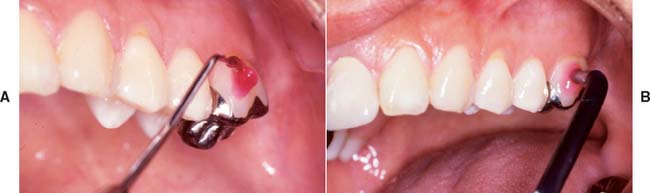

Patients should be instructed in special plaque-control measures, especially around pontics and connectors, and the use of special oral hygiene aids such as floss threaders (Fig. 32-2). If the pontics are properly designed (see Chapter 20), floss can be looped through the embrasure spaces on each side, and the loop can be pulled tightly against the convex pontic tissue surface. A sliding motion is then used to remove dental plaque (Fig. 32-3). Flossing under pontics is essential for improving prosthesis longevity. When dental floss is used, the mucosa beneath pontics remains healthy; without it, mild or moderate inflammation results.1 Tissue response has been shown to be independent of the pontic material.2

Fig. 32-3 The patient should be instructed in the use of floss to clean partial fixed dental prostheses.